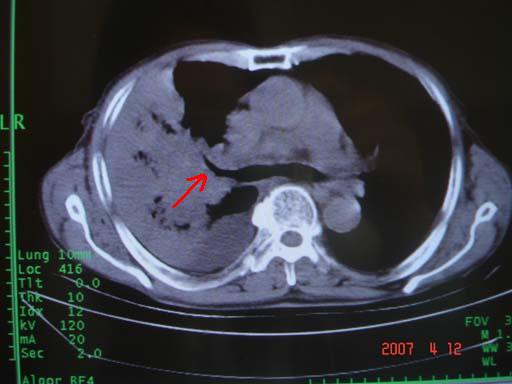

病灶局限在右肺中上叶,呈大片状实变影,内见空气支气管征,支气管分支较柔软,纵隔内未见肿大淋巴结.支持:感染性病变_1 大叶性肺炎.2 干酪性肺炎.

优先考虑右上肺干酪性肺炎并同侧中叶播散、胸腔积液。分析:右膈肌未见升高、纵隔未见明显右移,胸部各组淋巴结未见可疑肿大,中叶可见支气管铸形,肺野、肺门未见可确定肿块。

单从影像学上来看,该病人应首先考虑,右上肺感染(干酪性肺炎可能大)伴有右侧胸腔积液,理由如下:

1.病灶整体成宽基底征,而未见块状影

2.病灶内的透光区并不是含气支气管征,而像是坏死的肺组织后形成的

3.无肺不张的表现

4.纵隔那未见明显肿大淋巴结

结合病史,该病人尚需作进一步检查胸水,支气管镜,查痰等

右肺上叶后段支气管中断,首先考虑中央型肺癌并右肺不张及纵隔淋巴结转移,右侧胸腔积液。

右肺中心型肺癌可见支气管呈鼠尾状

有点象洗肉水的痰,其来源应当是实变引起的血细胞渗出导致,可见支气管气象,实变区有虫蚀状空洞,有明显胸腔积液,未见明显肺门区肿块影,考虑继发型肺结核,干酪性肺炎

右肺上叶实变,实变范围如此之大,如果用肺癌解释的化,应该是比较大的支气管开口发生完全阻塞,但观察上叶前后段支气管还是比较通畅,所以应考虑感染性病变,大叶性肺炎可能,建议抗炎治疗后复查。